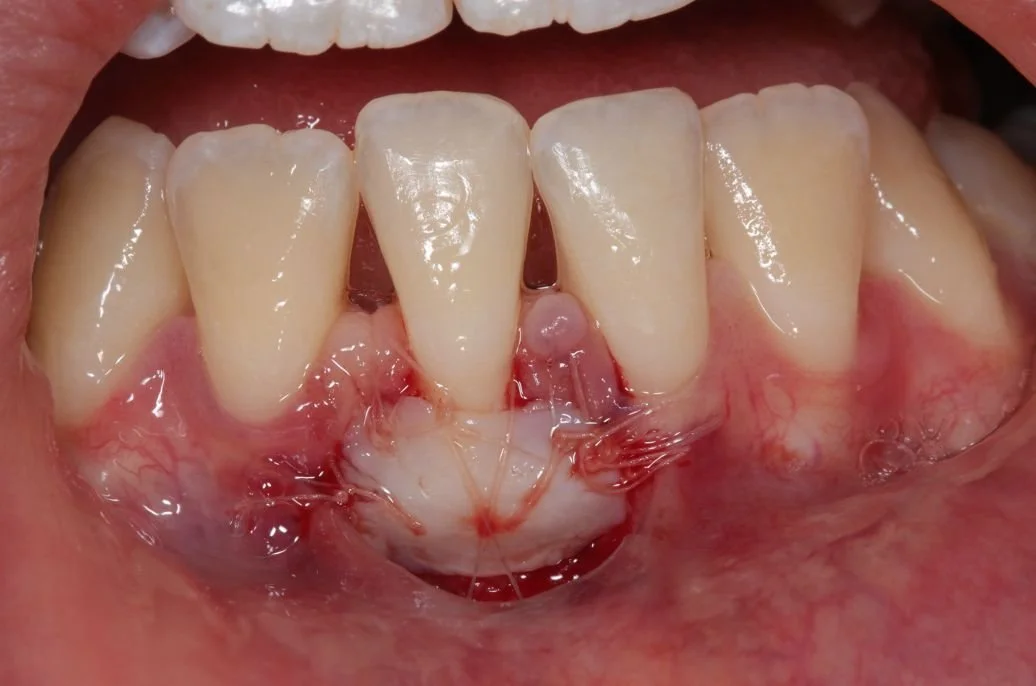

Open mouth showing a dark, bloodied lesion or tissue on the inner cheek or gum.

An example of the donor site of a gum graft - RW Perio